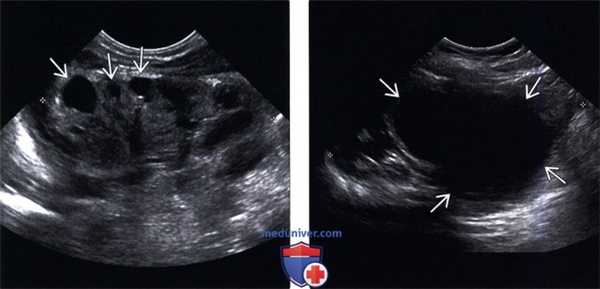

(Левый) На продольном УЗ срезе визуализируются диспластические кистозные изменения в верхнем полюсе почки, в результате обструкции, сопровождающейся потерей кортикомедуллярной дифференциации и истончением коркового вещества.

(Правый) На продольном УЗ срезе визуализируется значительное расширение лоханки нижнего отдела почки вследствие обструкции лоханочно-мочеточникового сегмента.